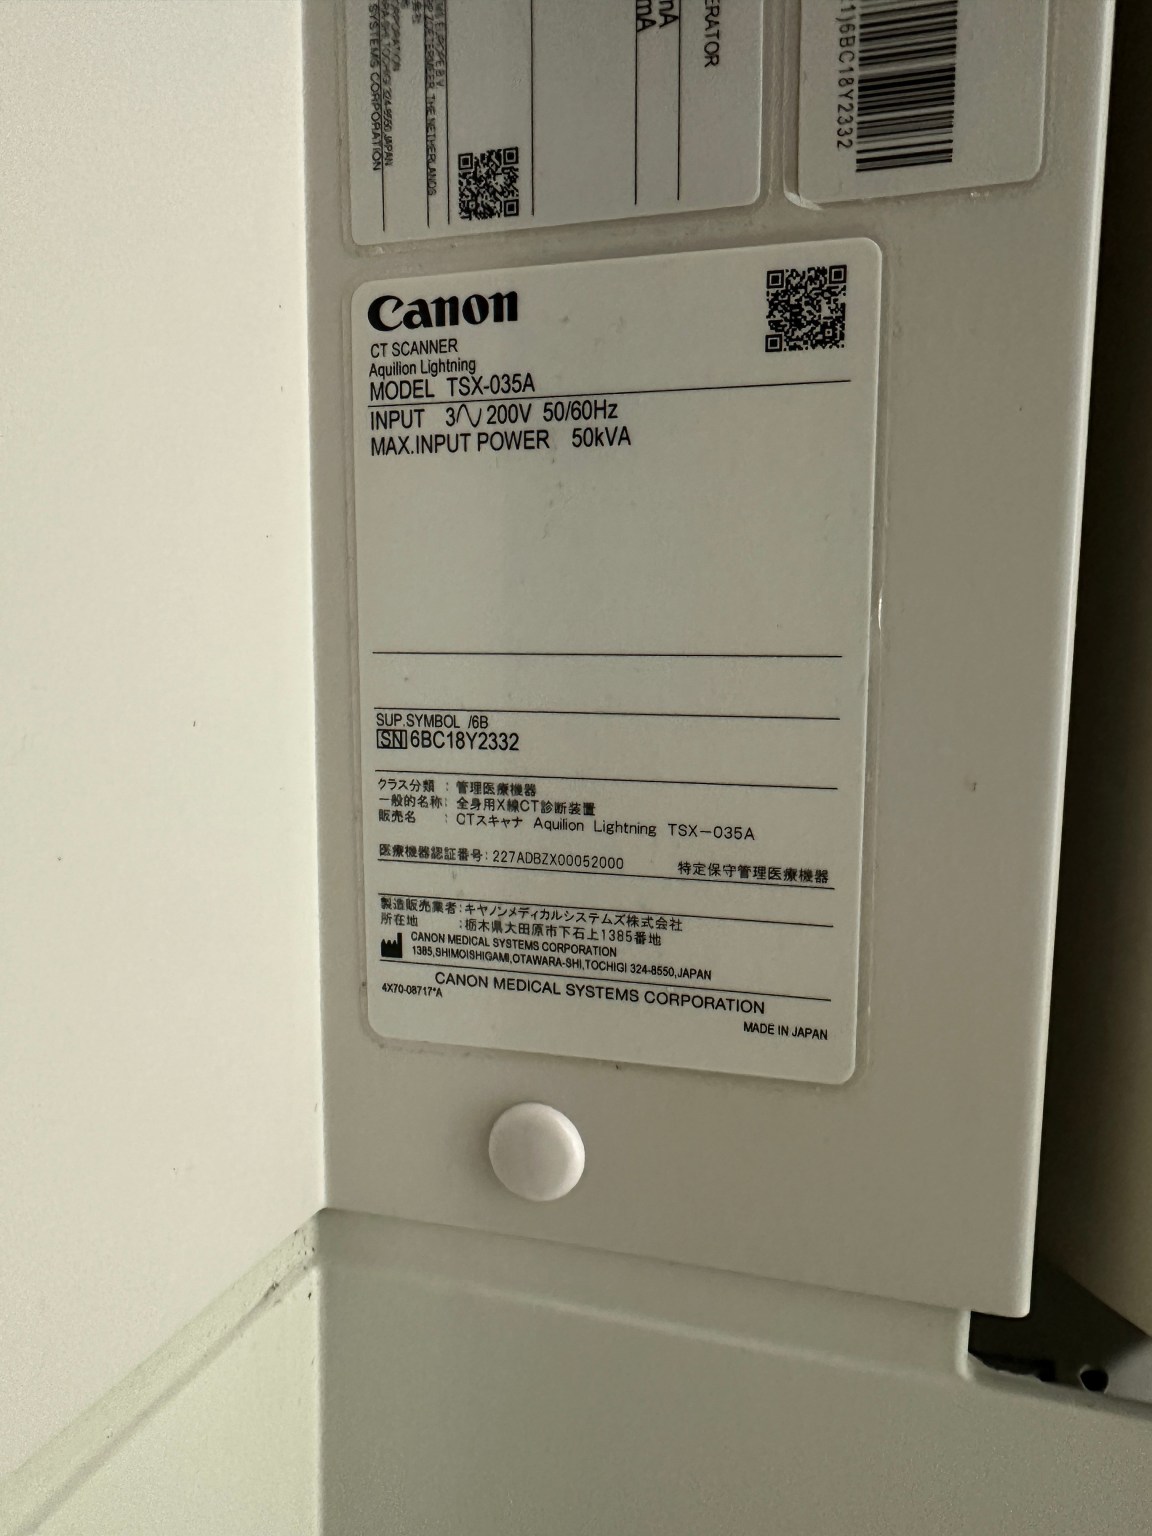

| Manufactured | : | November 2018 |

| Location | : | Japan (NEX325) |